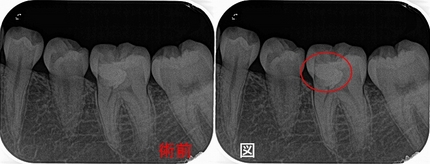

レントゲンで丸く黒く見えるもの

いつもブログでレントゲンの図で赤丸書いている丸く黒く見える部分ですが、

2026 EEdental TAK (1).jpg

患者さんに骨無くなってどんな状態!?と聞かれたのですが、

先日抜歯した歯にこの部分がくっ付いてきてくれたので

2026 EEdental SUM.jpg

骨が無くなり、こんな肉団子のような状況になっています。

専門的に言えば、「不良肉芽」というものです。

患者さんに分かりやすく伝える為に、レントゲンで膿と表現しますが、

炎症の急性期にはこの部分に膿が貯まっていることもありますが、慢性期にはこのような肉団子状態になっています。